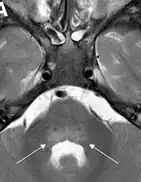

| Magnetic resonance imaging of the spinal cord in a case of AFM showing cord swelling in (d) which has resolved three weeks later in (e).[2] | |

Common features included acute focal limb weakness and specific findings on magnetic resonance imaging (MRI) of the spinal cord consisting of nonenhancing lesions largely restricted to the grey matter. In most cases, these lesions spanned more than one level of the spinal cord. Some also had acute cranial nerve dysfunction with correlating nonenhancing brainstem lesions on MRI. None of the children experienced altered mental status or seizures. None had any cortical, subcortical, basal ganglial, or thalamic lesions on MRI. Most children reported a febrile respiratory illness in the two weeks preceding development of neurologic symptoms. In most cases, cerebrospinal fluid (CSF) analyses demonstrated mild-moderate pleocytosis (increased cell count in the CSF) consistent with an inflammatory or infectious process.